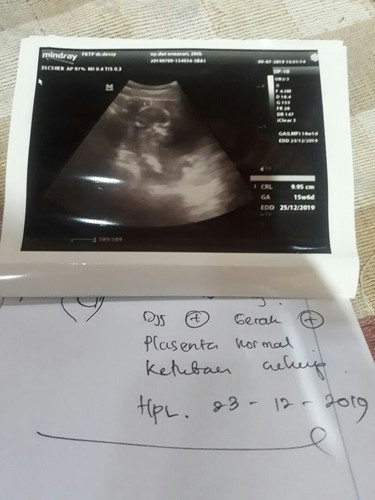

usg

Hay bun.. ini hasil usg aku.. Dedek nya udah bisa gerak2 tangan nya ? kata nya sih bb nya 100gr.. Kata dokter nya sih normal.. Klo menurut bunda2 normal gk ya??